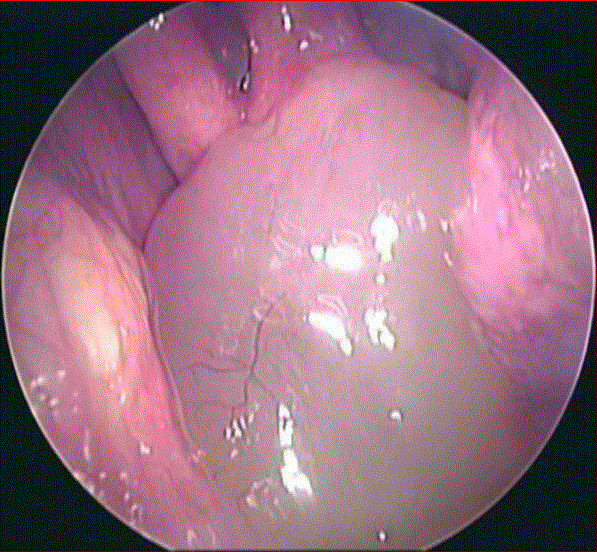

Vue endoscopique d’un polype nasal

L’endoscopie nasale

Elle permet à votre ORL d’effectuer un examen détaillé dans votre nez et de vos sinus. Il ou elle insère l’endoscope dans une narine et le guide dans votre cavité nasale.